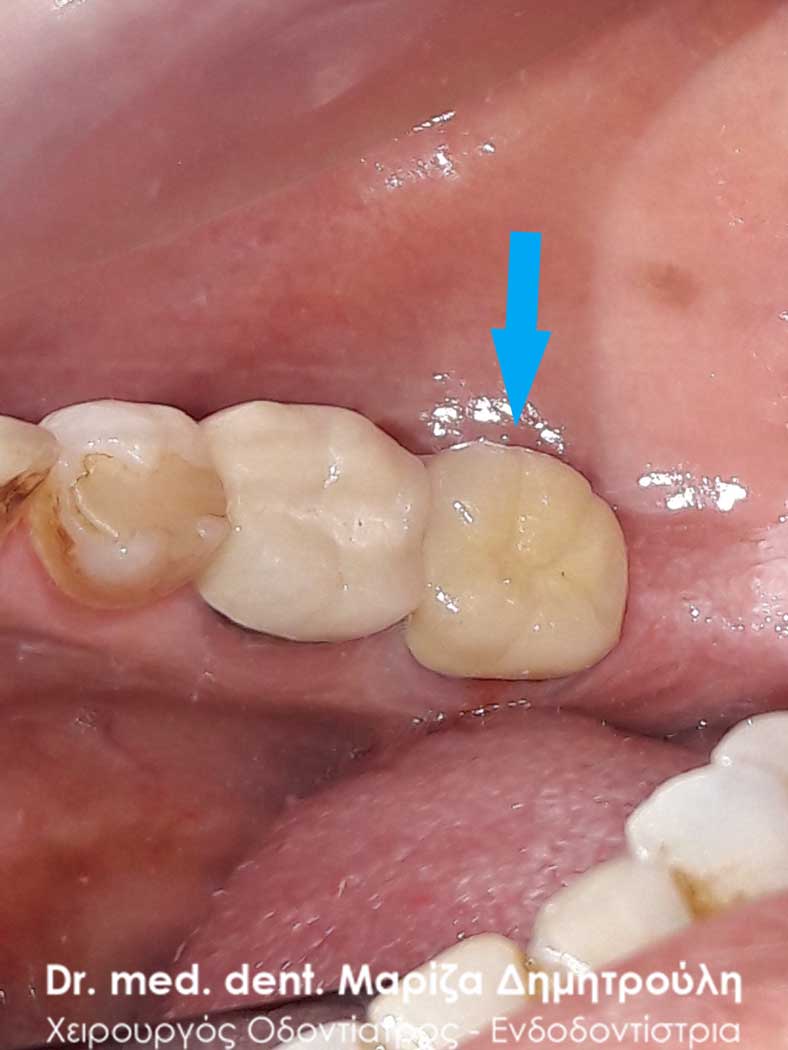

Τελική κλινική εικόνα του ολοκεραμικού ένθετου στον προγόμφιο